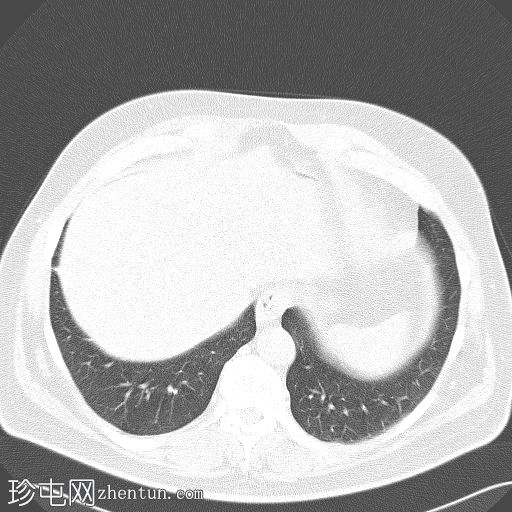

盆腔内可见一大小为12 x 17 cm的边界清晰的异质性软组织肿块,向下延伸至下腹部。肿块内未见钙化或脂肪密度影。肿块向下推挤膀胱,并牵拉周围肠袢,但无放射学侵犯证据。未见明显淋巴结肿大、腹水或气腹。未见肺部或骨骼局灶性病变。肝脏可见数个小的单纯性囊肿。患者存在少量Bosniak I型肾囊肿,双侧肾盂肾盏系统饱满。曾行胆囊切除术。